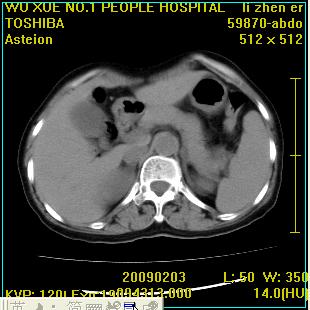

标题: CT18564:女,57岁,无不适,体验B超提示肾积水等 [打印本页]

标题: CT18564:女,57岁,无不适,体验B超提示肾积水等

左肾及左输尿管上端结石,左肾重度积水并左肾萎缩(不排除左肾先天性发育不良)。

左输尿管上端结石,左发育不良性多囊肾并积水;

右肾代偿性增大并肾盂积水,脾大。

左肾及左输尿管上端结石,基本上丧失肾功能了。

此患都左肾呈囊性变,边缘有高密度钙化,还是考虑结核吧.